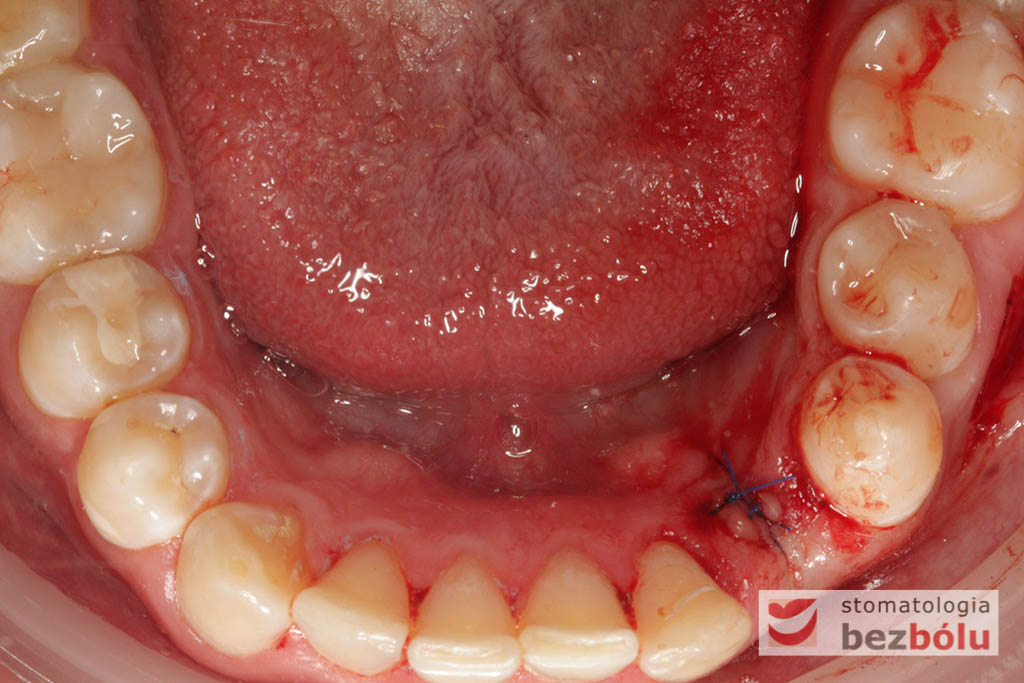

Procedurę chirurgiczną rozpoczęto od sprawdzenia przylegania szablonów do zębów pacjenta oraz znieczulenia miejscowego. W kolejnym kroku, przy pomocy specjalnie przeznaczonego do tego celu zestawu wierteł, wypreparowano krążki dziąsła punktowo odsłaniające kość a następnie poprzez tuleje prowadzące, z najwyższą precyzją, opracowano łoże implantu. Kulminacyjny moment zabiegu, czyli wprowadzenie wszczepów MIS C1 również odbyło się poprzez szablon, gwarantując precyzyjną lokalizację implantów. Zwieńczeniem całej procedury było przyszycie uprzednio wypreparowanych krążków śluzówkowo-okostnowych. Tuż po zabiegu, celem weryfikacji poprawnej pozycji implantów, wykonano zdjęcie ortopantomograficzne. Podczas wizyt kontrolnych, pacjent nie skarżył się na żadne dolegliwości bólowe, nie wystąpił obrzęk, a zreponowane we właściwych miejscach fragmenty dziąsła nie wykazywały oznak martwicy, co świadczyło o ich ponownym ukrwieniu i wgojeniu się. Wszystkie te przesłanki jasno wskazują na skuteczność zastosowania techniki komputerowej nawigacji w implantologii.